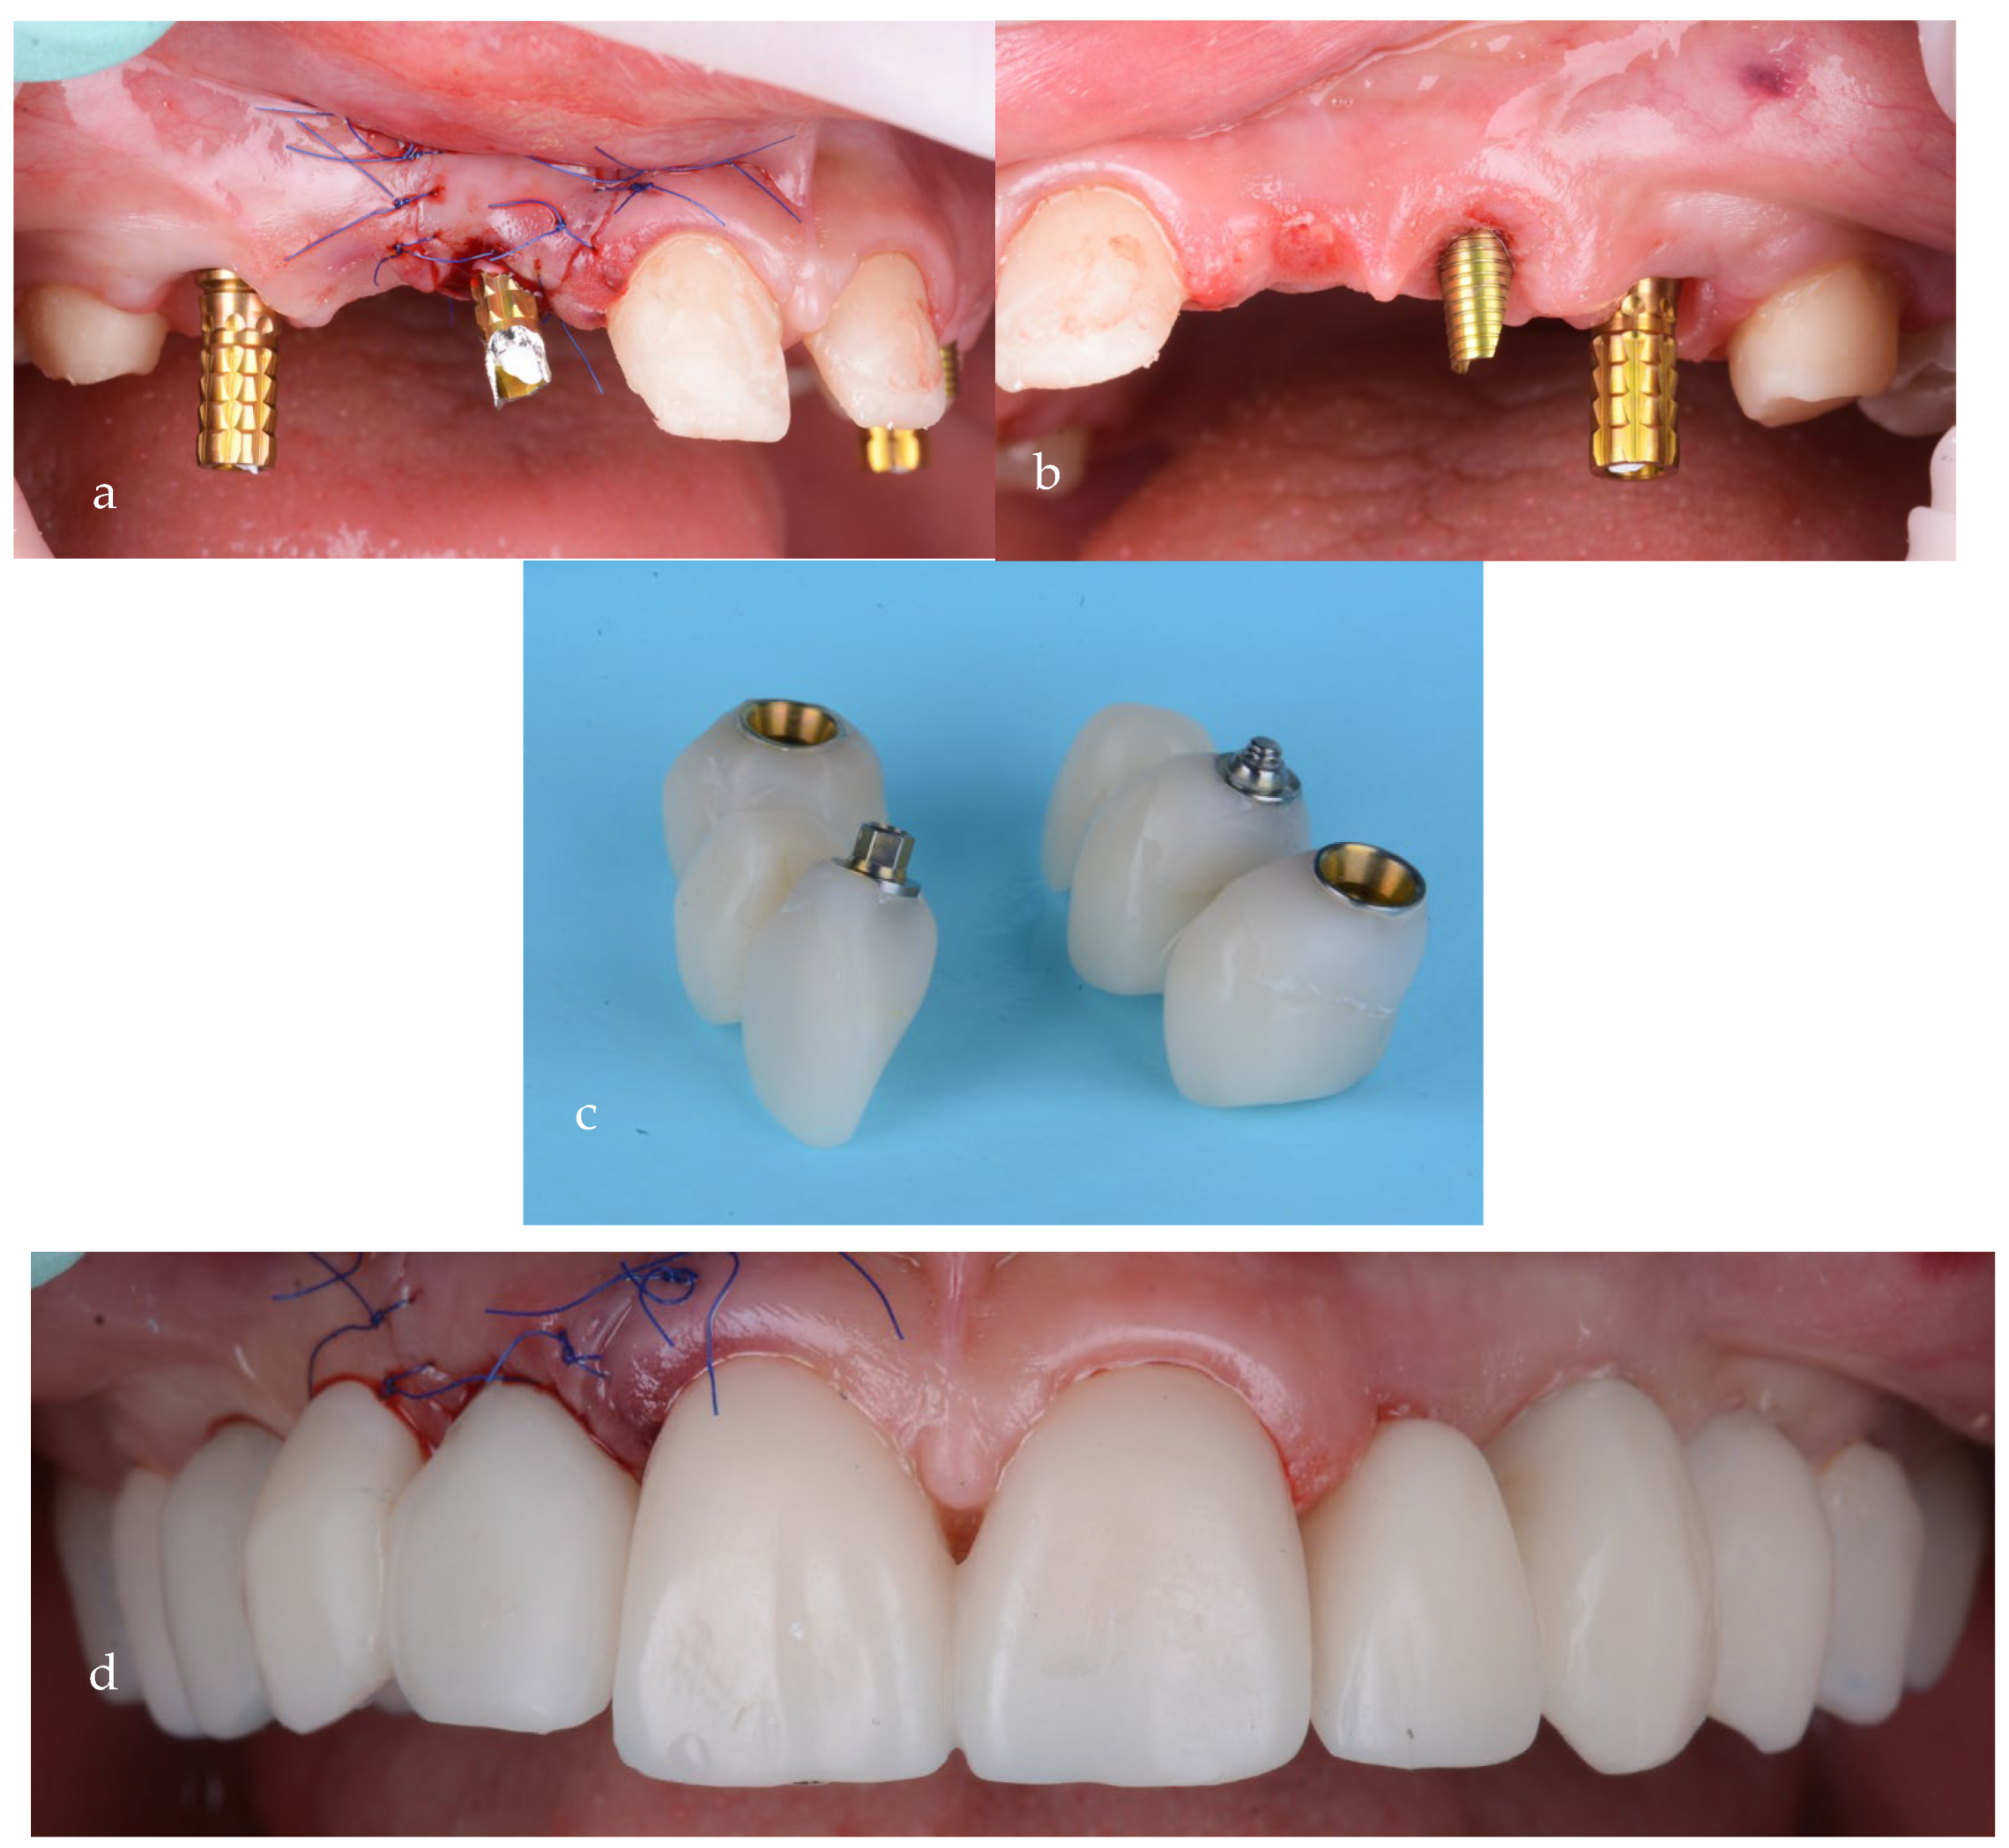

Temporary screw-retained bridges, with proper emergence profiles, were used at this stage for soft tissue shaping of the gingival contour (Figure 15a–d).

Figure 15.

Screw-retained provisional bridges on temporary abutments: (a) first quadrant, (b) second quadrant, (c) provisionals and (d) after intraoral cementation.

For the final restorations, monolithic zirconia was used for optimal biologic compatibility and superior strength (Figure 18a–f). The patient’s esthetics and function were fully restored. The intraoral pictures showed significant improvement in the micro esthetical characteristics. The gingival margins were levelled, and the teeth axes were corrected.

Figure 18.

Intraoral pictures of the result of monolithic zirconia-fixed partial dentures on teeth and implants: (a) upper incisors, (b) lower incisors, (c) right lateral view, (d) frontal occlusal view, (e) upper arch and (f) lower arch.